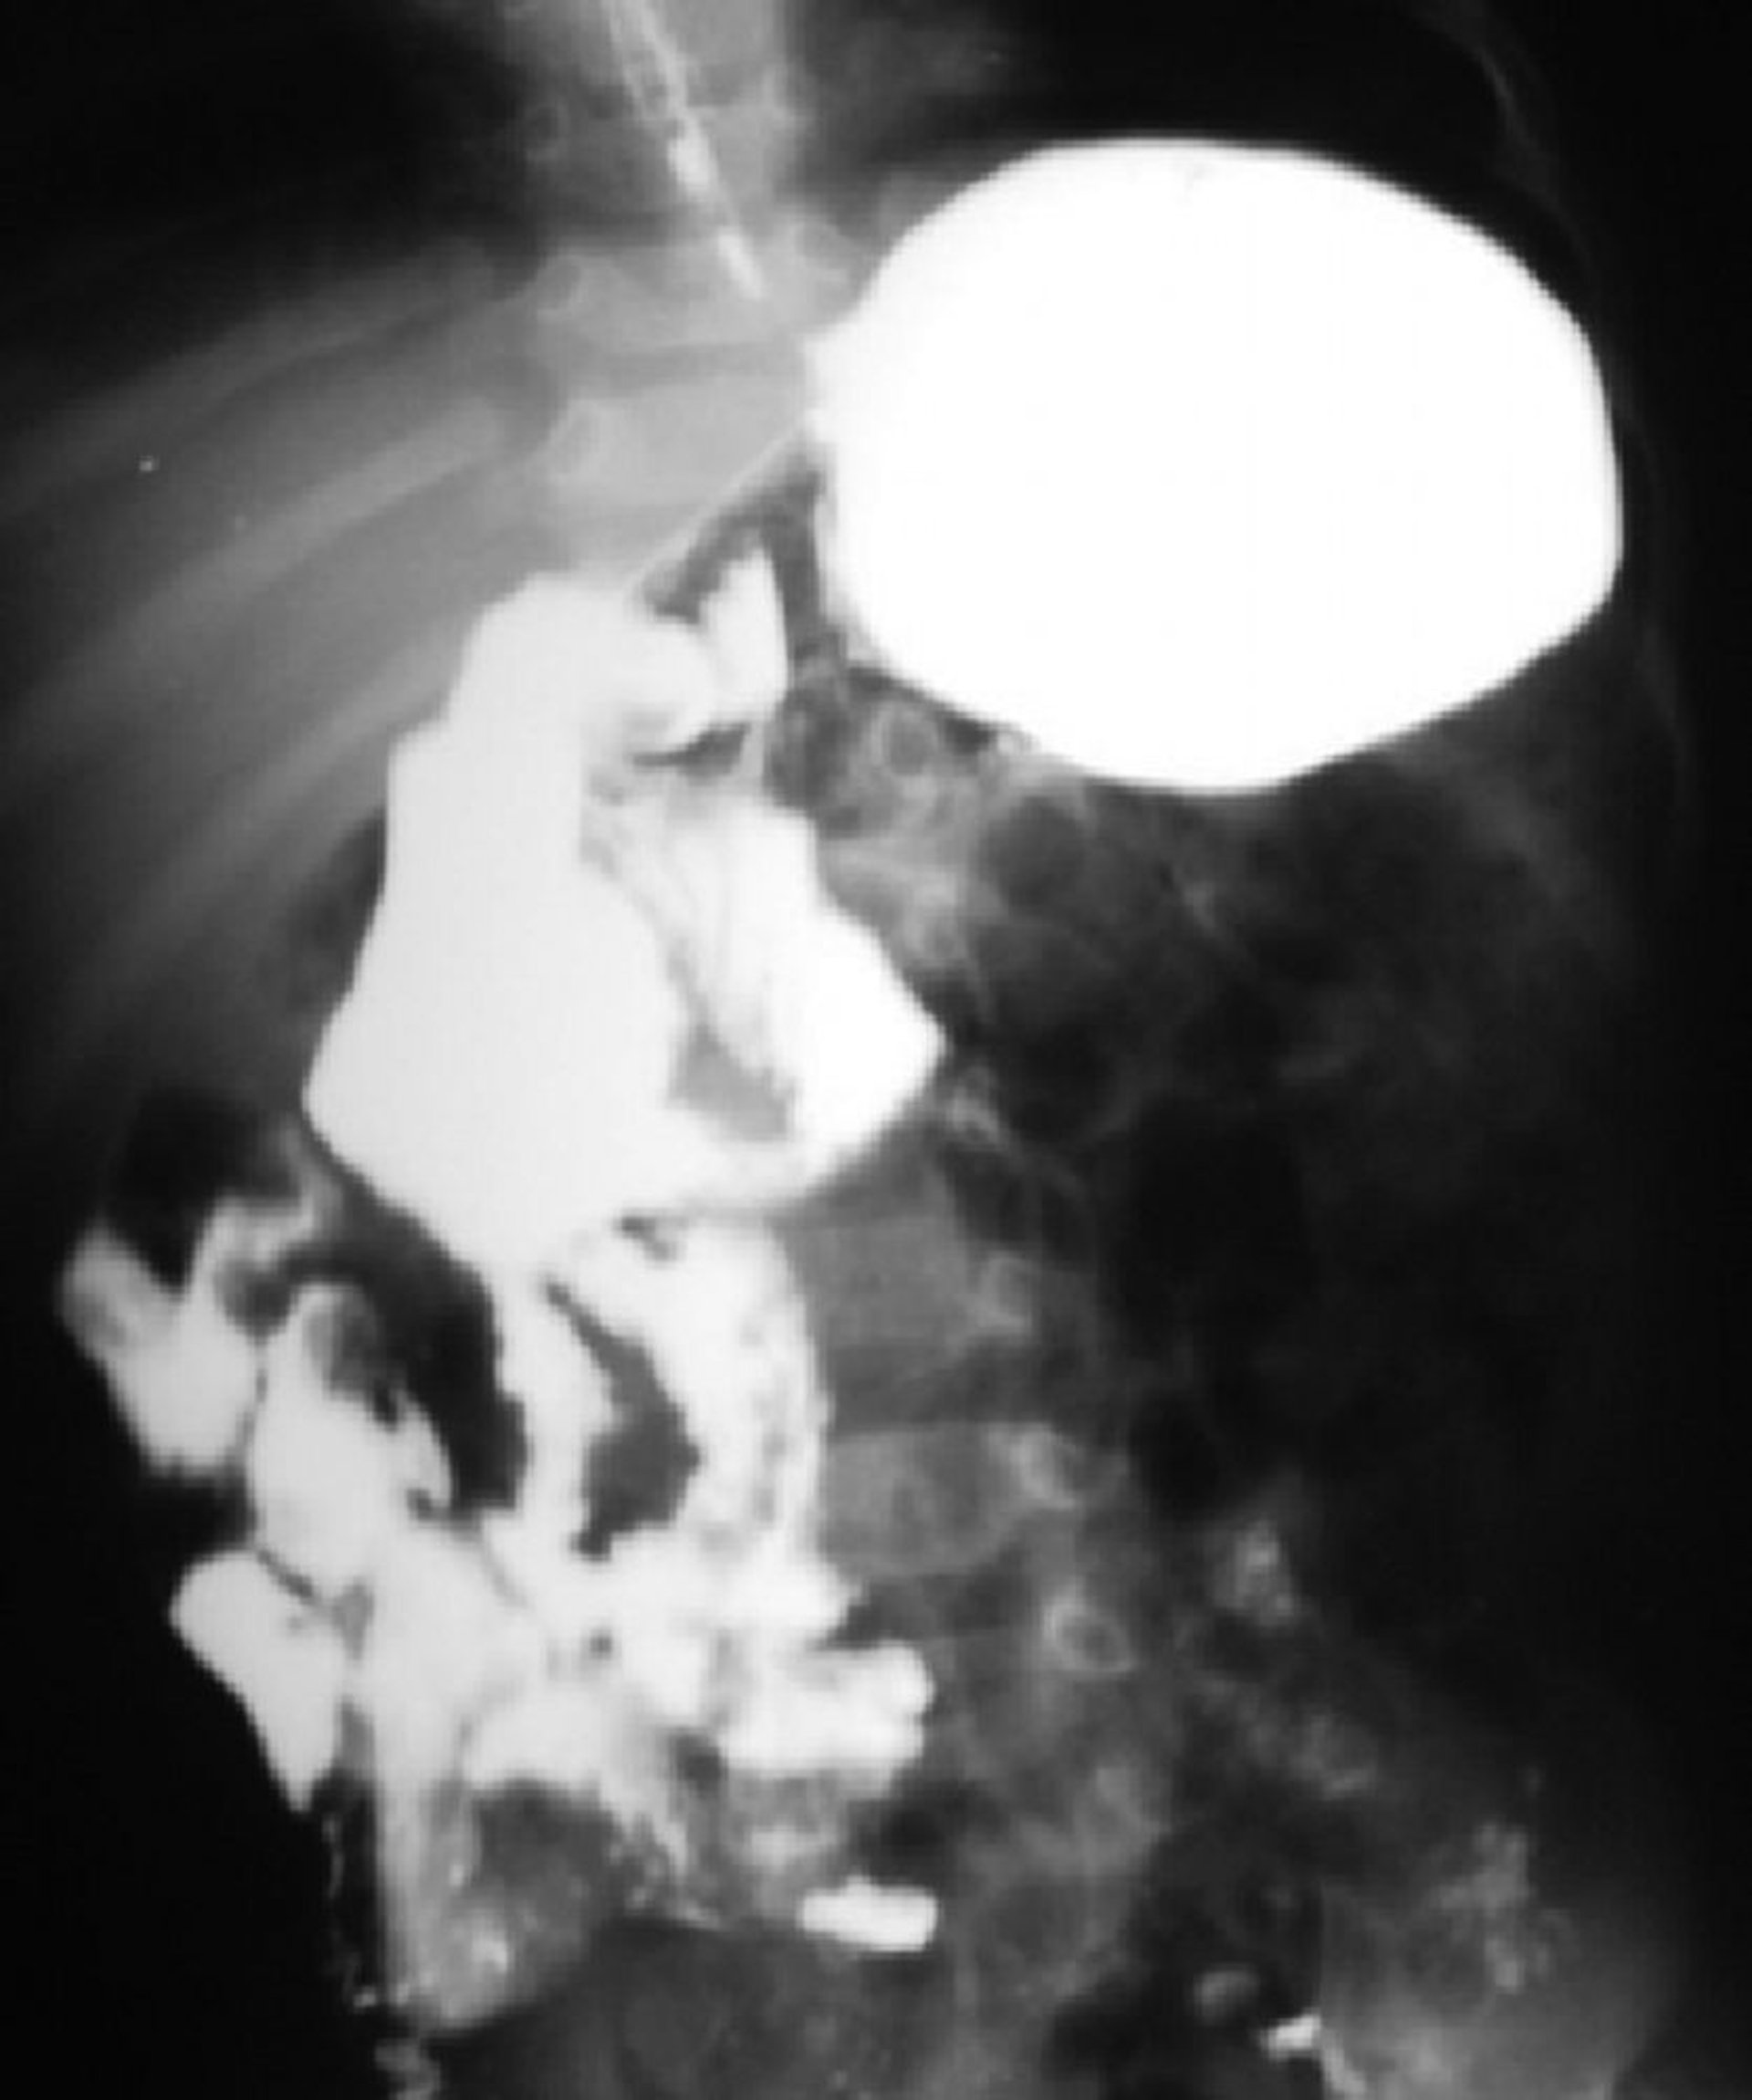

Malrotación intestinal

Este estudio con bario muestra malrotación del intestino. La unión duodenoyeyunal está a la derecha de la columna vertebral, y la mayor parte del intestino delgado está del lado derecho.